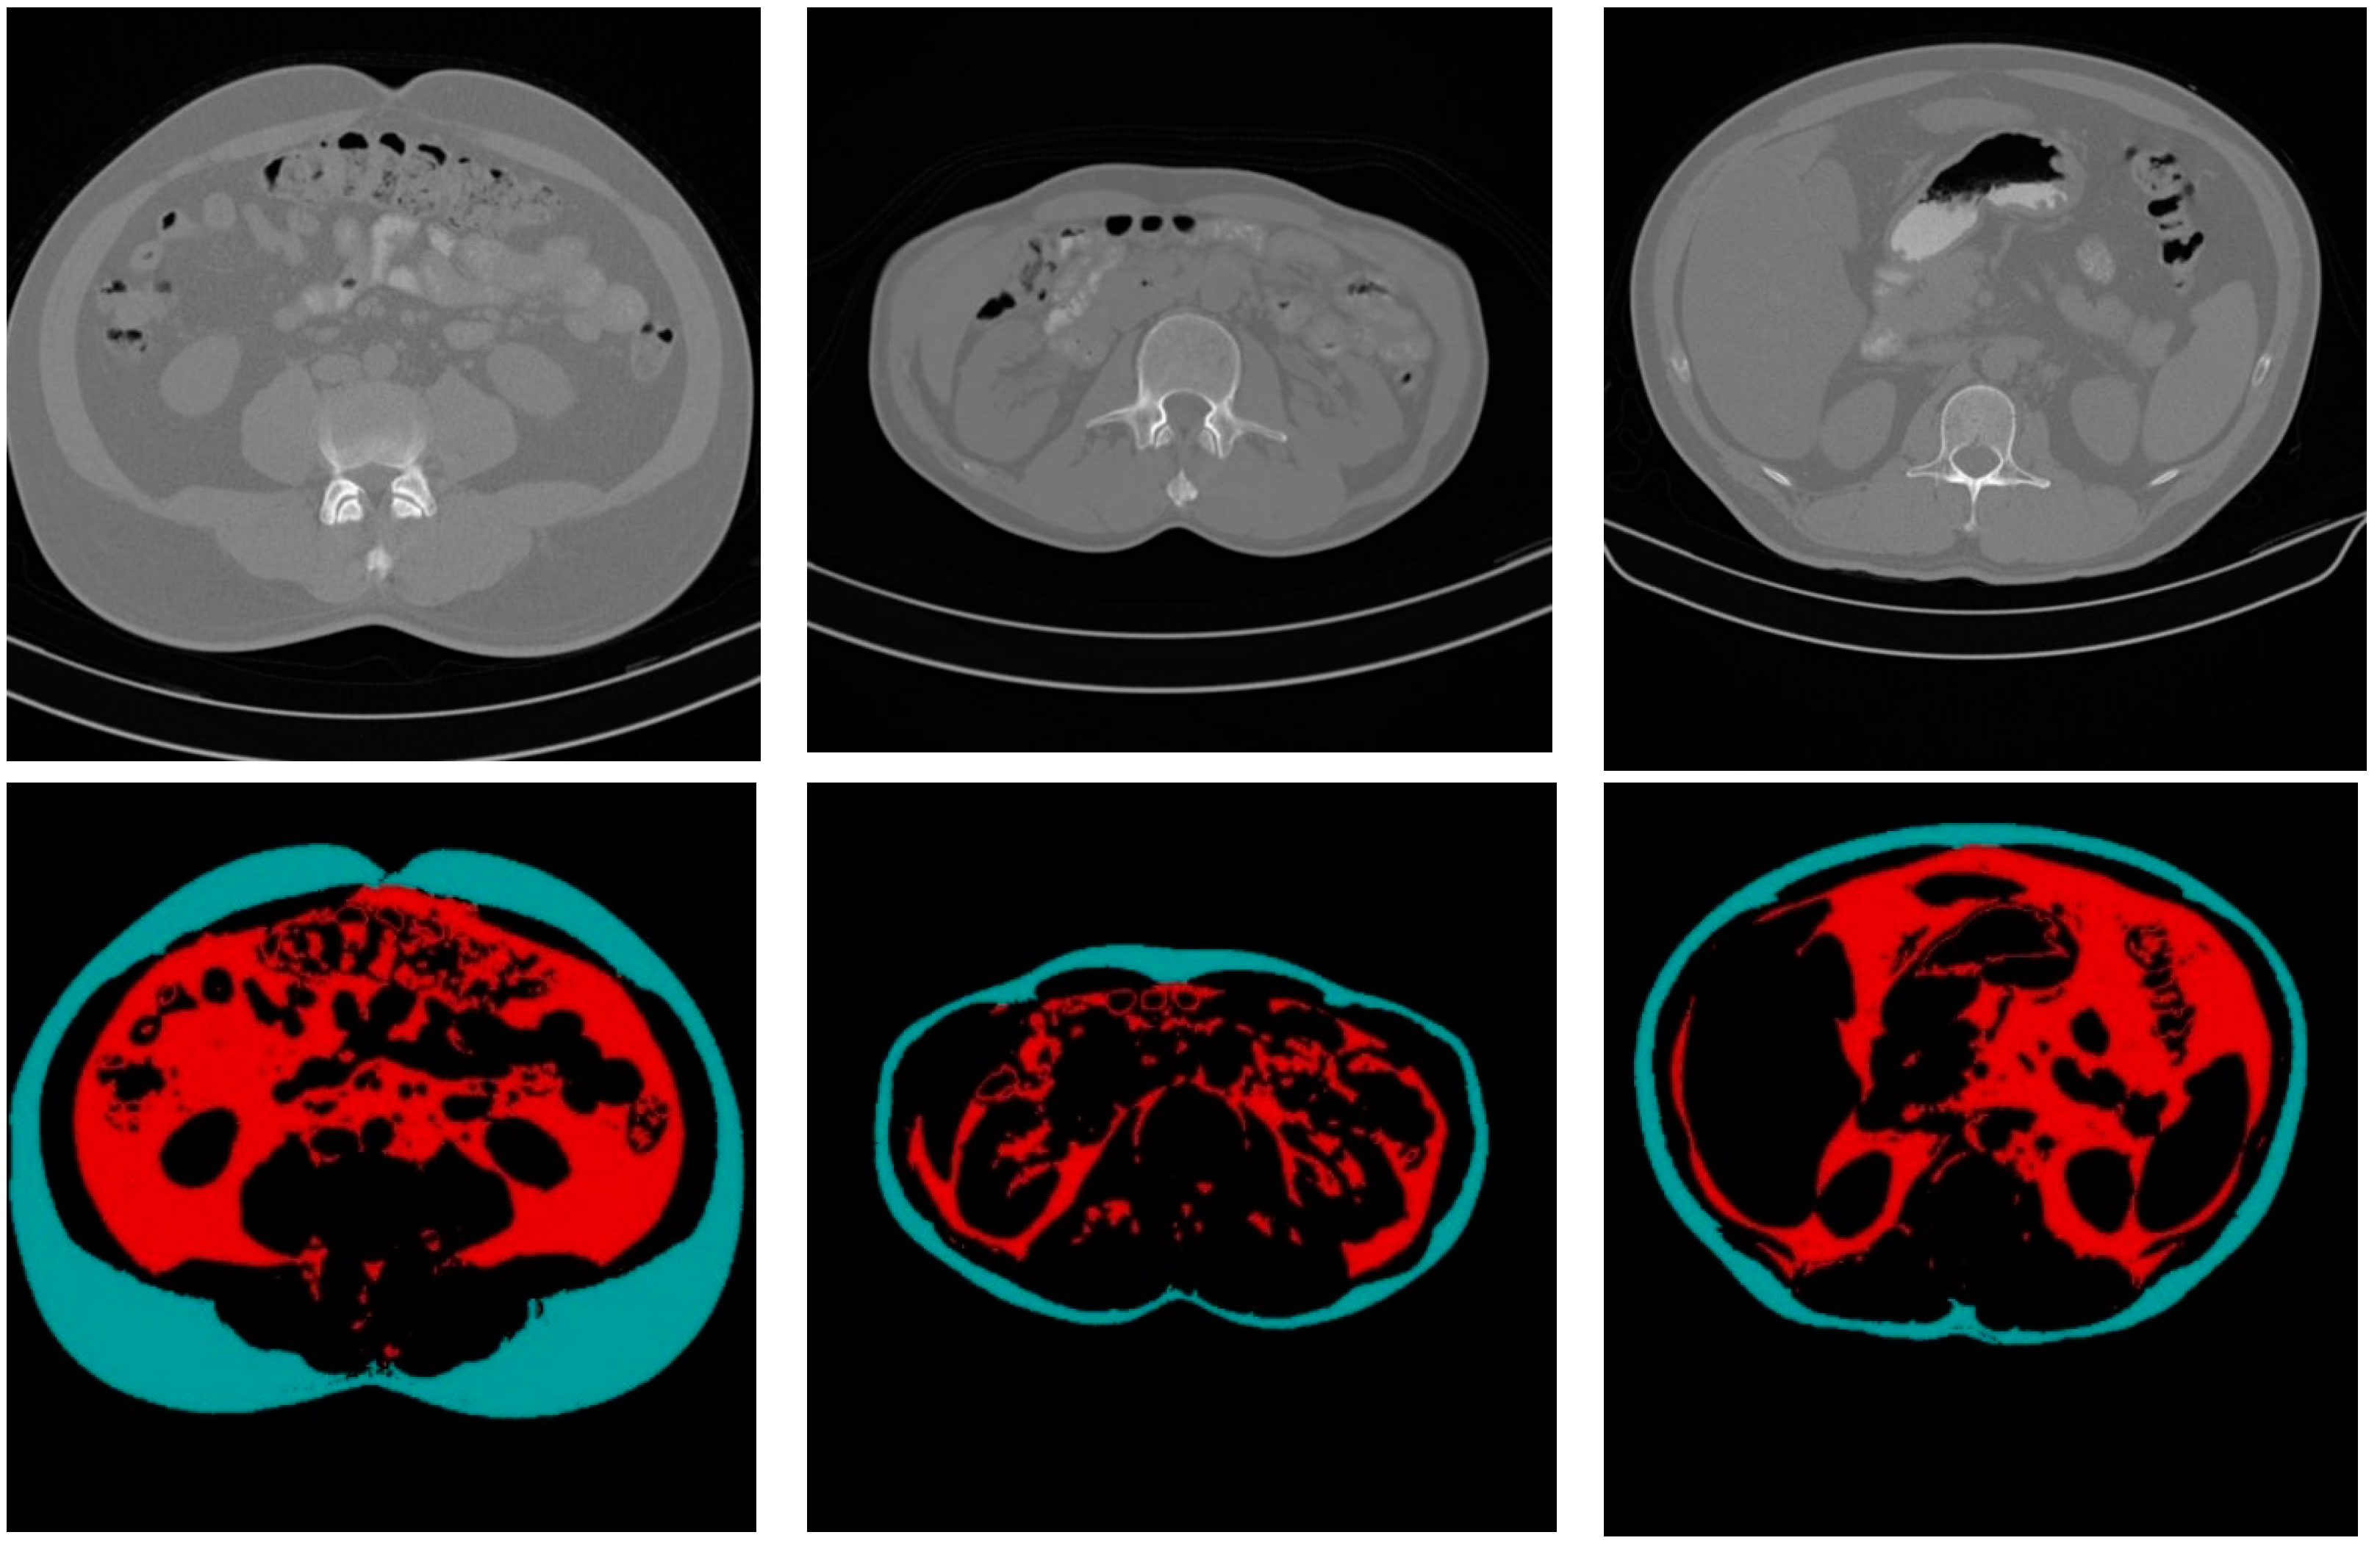

Figure 10 shows some CT sample images and the results of fat segmentation and classification. The top row images are the original DICOM images, and the bottom row presents the results of fat segmentation and classification for the top DICOM images. The red color region represents the VF tissue, and the turquoise color region represents the SF tissues.

Figure 10.

Samples of the original CT images and the results of fat segmentation and classification.